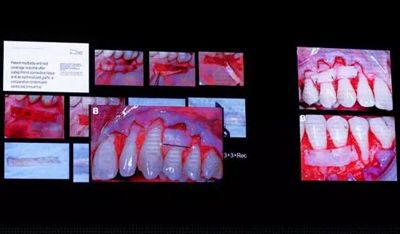

針對多牙位的牙齦退縮治療,齦乳頭區(qū)域的切口為斜行切口,同樣半厚-全厚-半厚翻開,相同的手術操作將齦瓣冠向復位。隨后進一步探討了牙齦退縮區(qū)域,不同術式的選擇。針對角化齦寬度大于2mm患者,僅用冠向復位瓣,就可以達到良好的治療效果。角化齦寬度1-2mm的患者如果組織厚度小于1mm,則應該使用雙層瓣技術。當角化牙齦寬度小于等于1mm時,也要使用雙層瓣技術。雙層技術僅在需要的牙位使用,長度為3+3+退縮寬度,寬度通常為4-5mm。需要注意結締組織不要覆蓋至根面冠方,它的作用是保持齦緣的穩(wěn)定,讓傷口自然的愈合。

最后Prof. Massimo de Sanctis展示了兩個復雜病例,病例一患者全口牙齦退縮,部分位點發(fā)生牙齒頸部的楔缺,同時存在頸部充填體,左上第一前磨牙有膿腫,頰側正中牙周探診達到9mm。首先去除頸部充填體,按照牙齦乳頭計算所得到位置重新進行頸部的充填。隨后進行根面覆蓋手術,術中發(fā)現(xiàn)左上第一前磨牙根面齲,去齲,EDTA處理根面,EMD進一步處理左上第一前磨牙根面,隨后使用結締組織覆蓋,冠向復位齦瓣,縫合。該病人取得了令人滿意的臨床效果。

病例二前牙牙冠邊緣侵犯生物學寬度,牙齦水腫,有深牙周袋,左上尖牙頸部充填體,左上尖牙、第一前磨牙,下頜前牙牙齦退縮。經基礎治療后,去除上切牙不良修復體,行根向復位瓣手術,骨修整手術后,重新制作修復體。左上尖牙去除充填體,重新充填。左上尖牙、第一前磨牙,下頜前牙使用雙層技術進行根面覆蓋。最終患者取得了良好的美學效果。